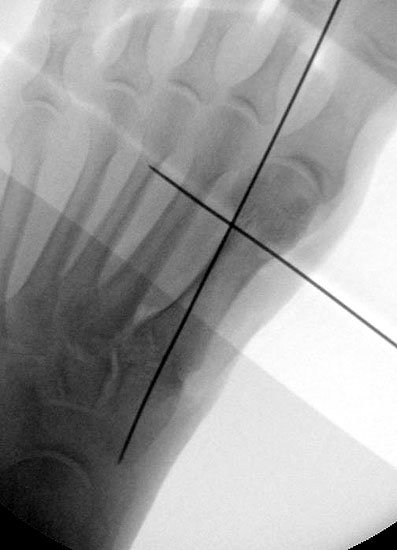

Röntgenaufnahme des Fußes im Stehen im dorsoplantaren und seitlichen Strahlengang (Abb. 1a-b).

Beurteilung des ersten Intermetatarsalwinkels (IMA), des Hallux valgus Winkels (HVA), des distalen (Distal Metatarsal Articular Angle, DMAA) und proximalen Gelenkflächenwinkels der Grundphalanx (Proximal Phalangeal Articular Angle, PPAA).

Abbildung 1a

Abbildung 1b